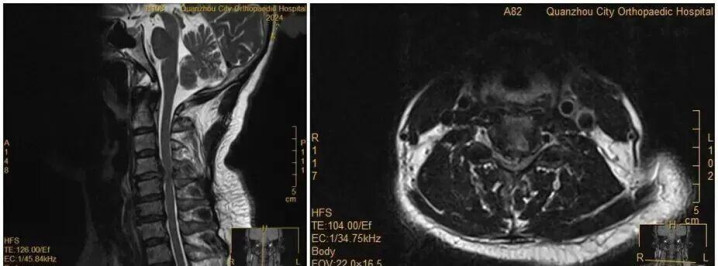

王女士术前MRI

没思到,诊断当晚,王女士翻身拿手机的眨眼间,双手遽然失去知觉——关键肌肌力降至1级或0级,确诊为瘫痪。“算计是翻身时,脱出的椎间盘遽然进一步卡压到脊髓神经,激励了急性症状。”医师示意。